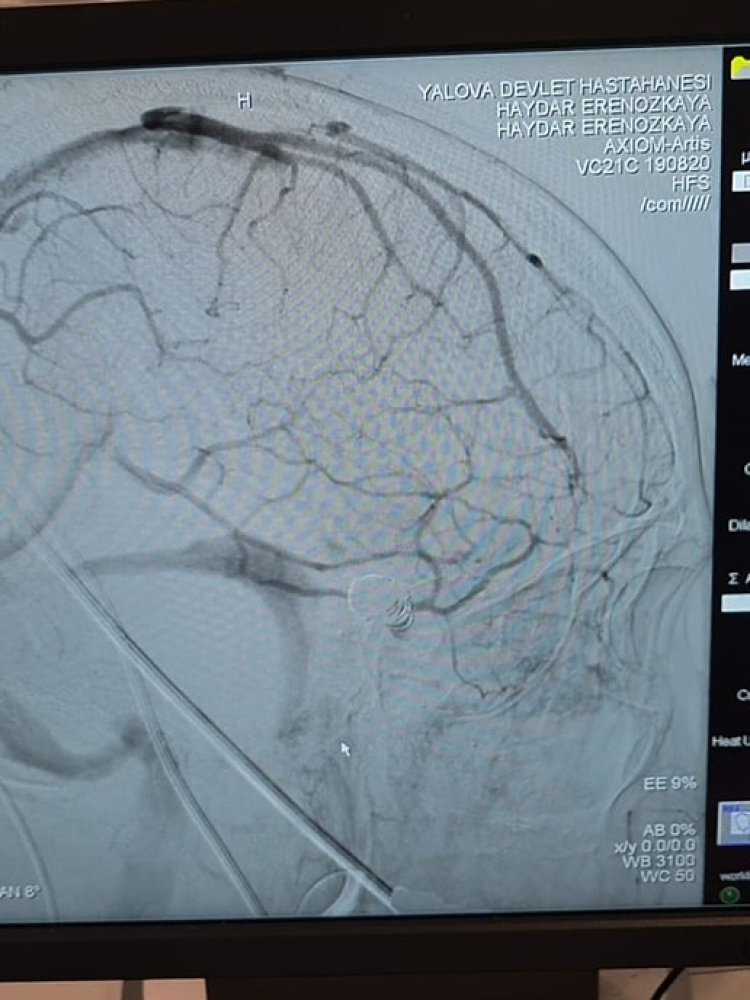

Yalova Eğitim ve Araştırma Hastanesi Acil Servisi’ne bilinci kapalı olarak getirilen 58 yaşındaki hasta, yapılan tetkiklerin ardından acil olarak endovasküler anjiyografi işlemine alındı.

Yalova Üniversetisi Tıp Fakültesi Öğretim Üyesi Dr. Haydar Eren Özkaya ve ekibi tarafından gerçekleştirilen operasyonda kasıktan girilerek yapılan coil ve stent uygulamasıyla anevrizma kapatıldı. Operasyonun ardından hastaneye komada gelen hasta bilinci açık şekilde uyandı ve kısa sürede yürüyerek taburcu edildi.